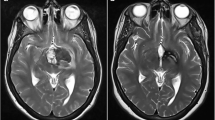

Cerebral cavernous malformations (CCMs) are low-flow vascular malformations composed of hamartomatous clusters of thin-walled capillaries, with an incidence of between 0.4 and 1.0% in the general population [1, 2]. The vast majority of patients do not experience any symptoms following diagnosis; however, a subset of CCMs are prone to haemorrhage, with a reported rate of 0.3–6% per patient year [3, 4].

Haemorrhages were classified in accordance with reporting standards from the Angioma Alliance [12], with a symptomatic haemorrhage defined as radiological (CT or MRI) evidence of acute haemorrhage, associated with acute or subacute clinical symptoms. ‘Interval change’ during follow-up was defined as a change in signal intensity on T2-weighted MRI scan, without symptoms suggestive of haemorrhage. Size was measured as maximum diameter including surrounding hemosiderin on T2-weighted, 1.5- to 3-T MRI imaging, as described previously [8]. If multiple intracranial lesions were present, for the per-patient analysis, we used the median diameter of combined cavernoma. If no genetic testing was completed, a familial cerebral cavernous malformation (FCCM) was defined by established criteria as the presence of both: diffuse CCM (five or more) or occurrence of CCM in at least two first-degree family members. In patients with genetic testing available, FCCM was defined as confirmation of one of three genetic mutations known to be associated with FCCM (CCM1, CCM2, and CCM3) [13, 14]. Follow-up duration was defined as the time in months from initial diagnosis until last clinic review with a neurosurgeon.

Of the 734 CCMs, 411 (56.5%) were located in the cortex, followed by subcortex (21.4%, N = 156), brainstem (13.1%, N = 96), and cerebellum (8.9%, N = 65). Located in an eloquent brain area (N = 331) were 45.1%. The median diameter of CCM was 11 mm (IQR 7–15, range 2–65).

The factors associated with haemorrhage are shown in Table 2. On univariable analysis, factors associated with haemorrhage were increasing size (HR 1.05, 95% CI 1.02–1.08, P = 0.002), eloquent area (HR 2.60, 95% CI 1.12–6.04, P = 0.026), and symptomatic haemorrhage at presentation (HR 5.64, 95% CI 2.53–12.58, P < 0.001) (Table 2). On multivariable analysis, the significant factors for haemorrhage were size (HR 1.04, 95% CI 1.01–1.07, P = 0.004), eloquent area (HR 2.63, 95% CI 1.12–6.16, P = 0.026), and symptomatic haemorrhage at presentation (HR 5.37, 95% CI 2.40–11.99, P = 0.001) (Fig. 3). None of the covariates in the Cox regression were significantly time dependent on Schoenfeld residual testing (Supplementary Figures 1 and 2), indicating proportional hazards. A linear relationship was observed with increased cavernoma size and risk of haemorrhage, when using binary size definitions (Table 3).